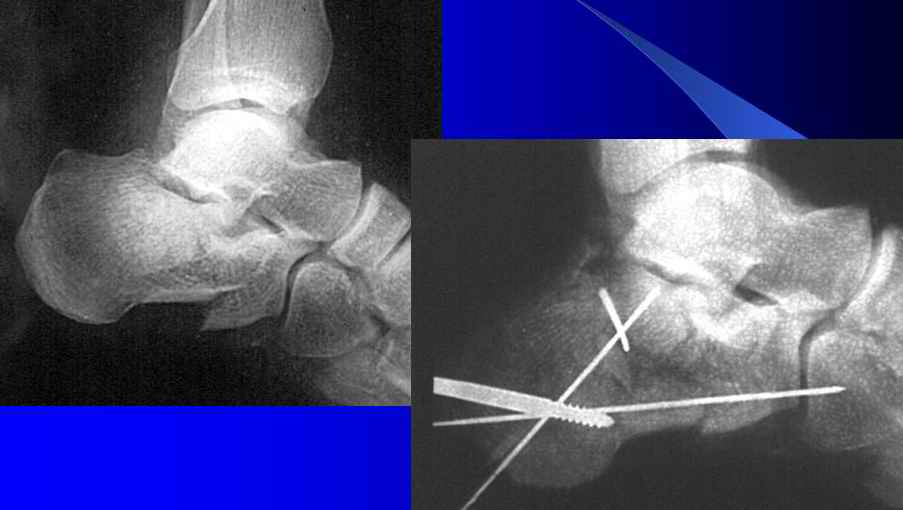

Уважаеемый коллега.Слева ситуация достаточно не сложная.Суставной фрагмент вклинился в тело.Необходимо наружным доступом освободить отломки,поднять суставной фрагмент и фиксировать пяточной пластиной LCP.

Результат посылаю отдельно.На предыдущих рент. видна репозиция.

Справа ситуация сложнее так как имеется помимо перелома имеется вывих тела пяточной костиПоэтому даже если удастся достигнуть хорошей репозиции необходимо сделать первичный подтаранный артродез.Иначе кость не будет держать в своём ложе.Но пластина нужна обязательно чтобы восстановить форму пятки.С уважением Дрягин

Otkritaya repositsija, fixatija plastinoj. Sprava podtaranniy artrodez.